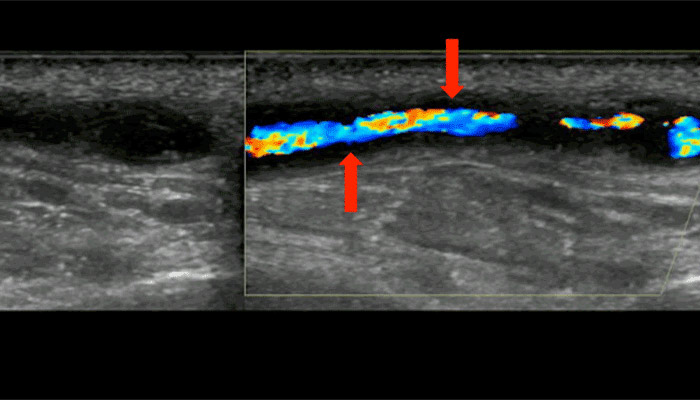

Ultrasound view, along the length of a branch of the temporal artery. The blood flowing in the artery is colored; the dark area on both sides (see arrows) is caused by swelling the wall of the artery, due to giant cell arteritis.